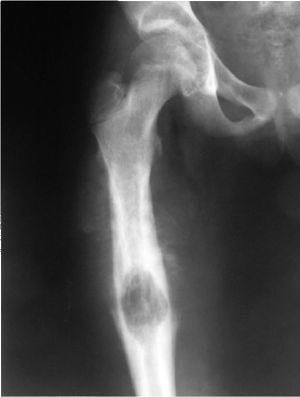

Остеогенная саркома – злокачественная опухоль, клетки которой развиваются из костной ткани. Данная опухоль чрезвычайно злокачественная и характеризуется бурным течением и ранним разрастанием метастазов. Рентгенологически саркома подразделяется на остеоплатсическую (склеротическую), остеолитическую и смешанную формы.

Остеогенная саркома может возникать в любом возрасте, но большинство случаев приходится на возраст от 10 до 30 лет, причем, мужчины болеют в 2 раза чаще женщин. Самая распространенная локализация опухоли в трубчатых костях нижних конечностей, реже поражаются плоские и короткие кости. Излюбленное место новообразования – коленный сустав, далее идет бедро, на долю которого приходится 50% всех сарком данного типа. Располагаться опухоль может также в большеберцовой, малоберцовой, локтевой, тазовой, плечевой кости. Череп поражается остеогенной саркомой преимущественно у детей или в старости, как осложнение остеодистрофии.

Начало развития опухоли определить вовремя трудно, поэтому так часто люди попадают в больницу с уже запущенными саркомами. Сначала могут появиться тупые боли в области сустава без признаков выпота. Часто это тот сустав, который в прошлом пострадал от травмы. По мере роста образования в процесс вовлекаются соседние ткани и боль увеличивается. Появляются явные утолщения метадиафизарного отдела кости, пастозность тканей, венозная сеточка кожи. В этот период уже явна контрактура сустава, появляется хромота. При прощупывании сустава пациент ощущает сильную болезненность.

В ночное время боли не проходят, не утихают они даже при приеме анальгетиков или фиксации конечности в гипс. Опухоль молниеносно разрастается на соседние ткани, заполняет костномозговой канал, проникает в мышцы, очень рано обширно метастазирует. Гематогенные метастазы проникают в головной мозг, легкие, в кости метастазы наблюдаются очень редко.

- Рентгенография, в частности с контрастным веществом.

Несмотря на такие прогрессивные методы диагностики саркому на начальных стадиях выявить практически невозможно. По одним только симптомам сложно судить о подлинности заболевания. При диагностике остеогенную саркому следует дифференцировать от хондросаркомы, хрящевого экзостоза, эозинофильной гранулемы, остеобластокластомы.